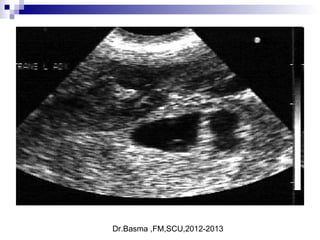

ultrasonographic diagnosis

 Definitive ultrasonographic diagnosis of an ectopic pregnancy is made in

only about 20% of cases, when an extrauterine pregnancy is clearly

identified (ie, an extrauterine gestational sac with a yolk sac or fetal pole is

visualized).

 numerous findings that are highly suggestive of ectopic pregnancy,

including

1. an empty uterus in a patient with a β-hCG level above the discriminatory

zone,

2. an adnexal mass other than a simple cyst .

3. echogenic fluid in the cul-de-sac, or anything more than a small amount of

fluid in the cul-de-sac.